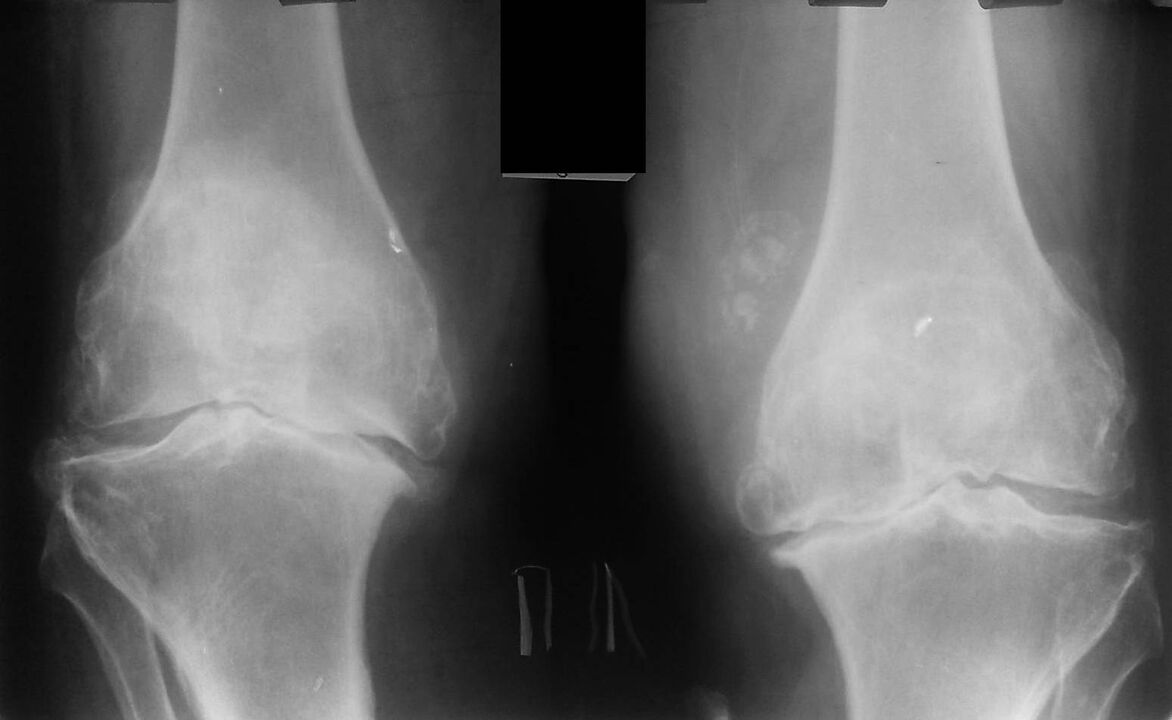

O spray Hondrox é un remedio para a dor nas articulacións. O medicamento úsase no tratamento e prevención da artrite, artrose e outras enfermidades articulares. O spray Hondrox ten unha composición natural, ten un poderoso efecto antiinflamatorio e rexenerativo, alivia a dor e o inchazo. España recoñeceu a eficacia do spray Hondrox para o tratamento e prevención de articulacións, o produto pódese solicitar no sitio web oficial e Ciutadella está entre os asentamentos coa entrega do produto.